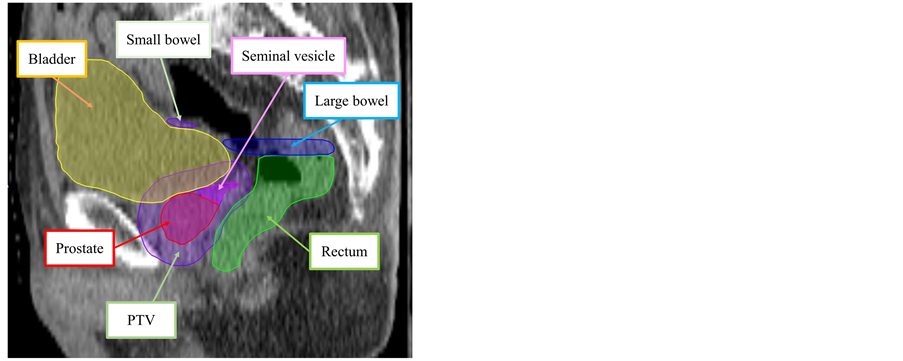

XiO version 5.00 (Elekta, Stockholm, Sweden) was the Radiation Treatment Planning System (RTPS) used. Target and organ volumes were determined, based on the planning CT images, by a radiation oncologist and a medical physicist. Figure 2 shows the example of target and organ volumes determined in this study. A prostate clinical target volume (CTV) and planning target volume (PTV) were defined. The CTV was the prostate with 10 mm of the proximal seminal vesicle. All seminal vesicles were included in the CTV (in cases of clinical T3b stage disease). PTV was defined as the CTV plus a 10 mm margin (rectal side: 5 mm). The OARs were the rectum (from the ischial tuberosities to the rectosigmoid flexure), the rectal wall within 10 mm above and below the PTV (wall thickness: 4 mm), the bladder, the bladder wall (wall thickness: 4 mm), and the small and large bowels. The bladder volume was calculated using the planning CT images.

Figure 2. The example of target and organ volumes determined in this study.